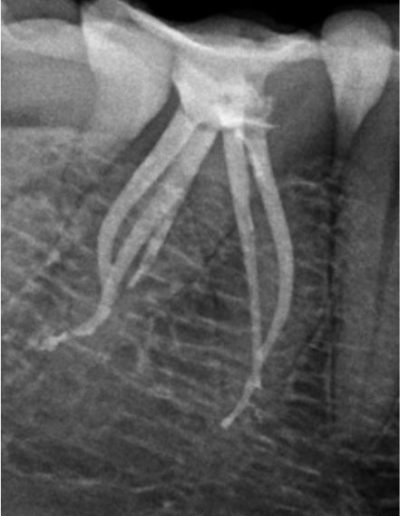

最小限の冠状動脈アクセス